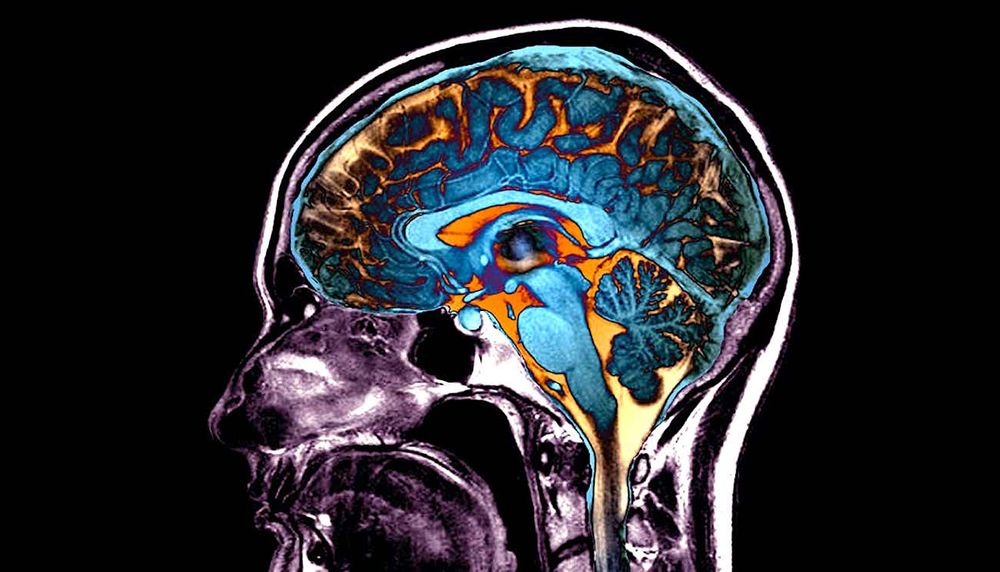

Les modifications cérébrales provoquées par la COVID auraient un impact sur la conscience et la cognition

Les effets de la COVID-19 sur le cerveau font partie des nombreux mécanismes encore peu compris de la maladie. Plusieurs études ont fait la lumière sur des processus pouvant expliquer les symptômes et altérations observés chez de nombreux patients. Il a notamment été démontré que le SARS-CoV-2 peut altérer le fonctionnement cérébral jusqu'à une modification profonde de la conscience, de la cognition et du comportement. Certains experts craignent également d'autres effets à très long terme de l'infection, dont l'augmentation du risque de démence plus tard dans la vie.